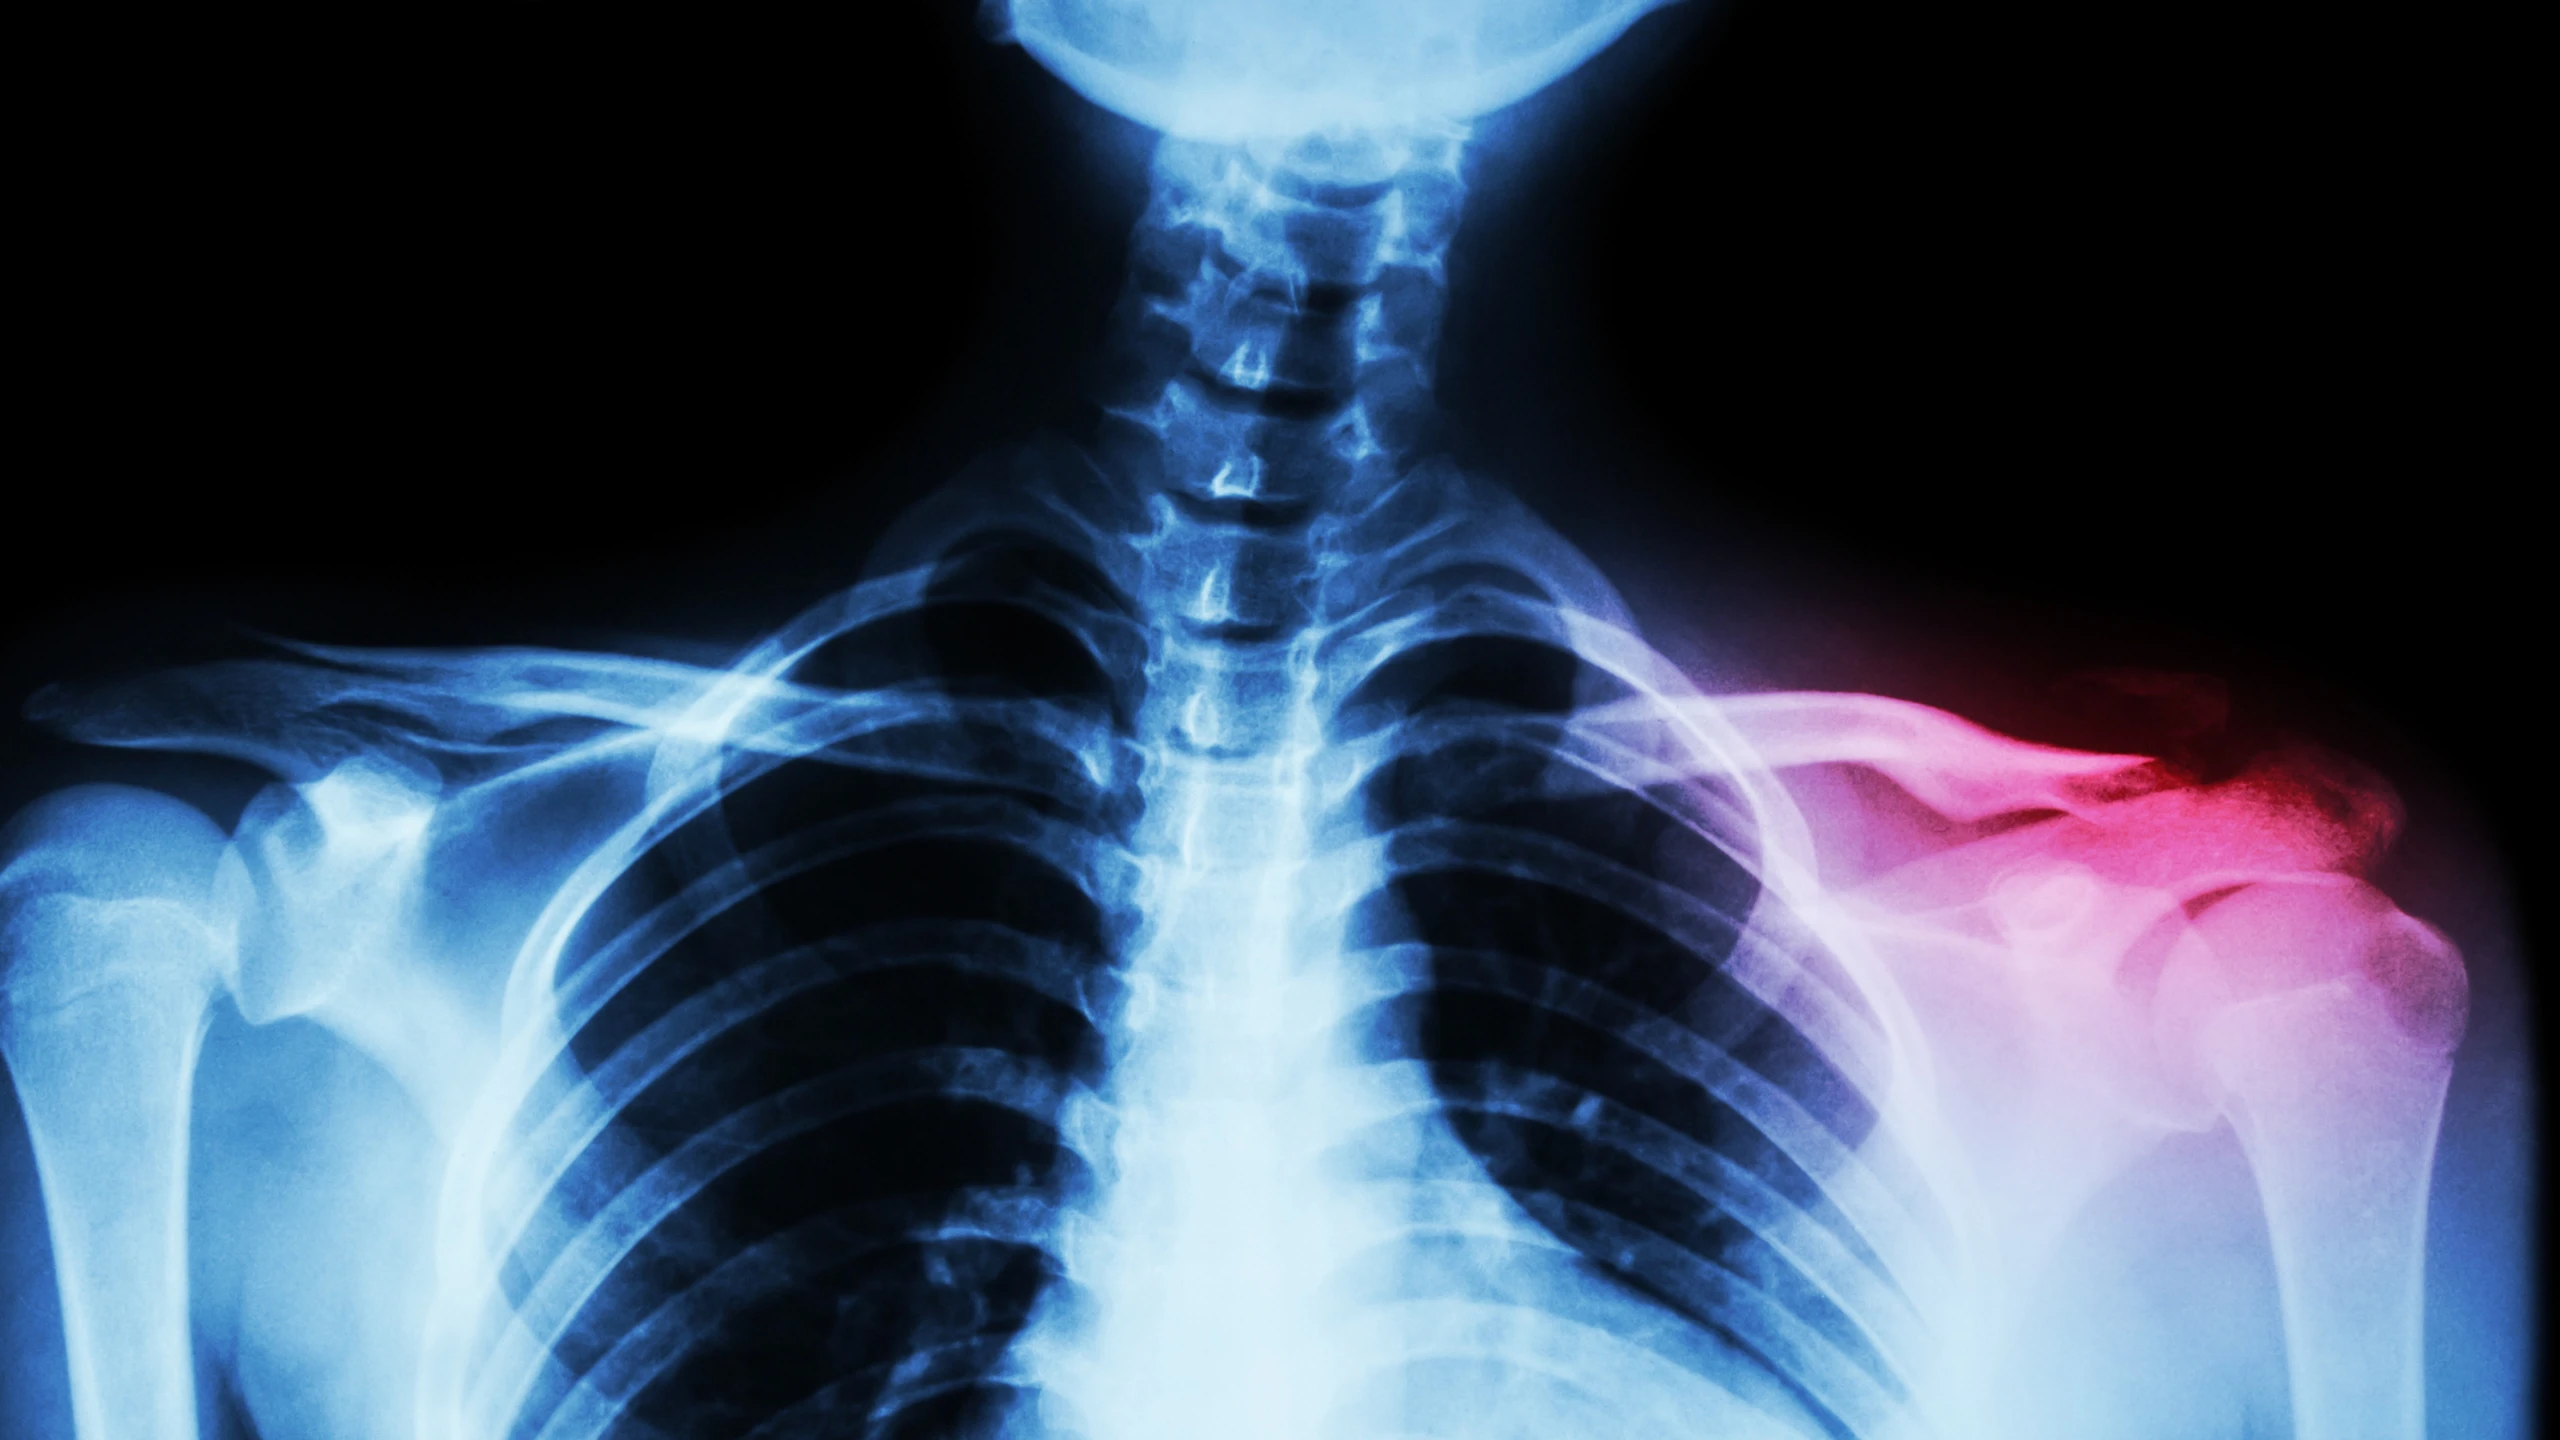

- Chụp X-quang xương đòn: Đây là phương pháp chẩn đoán hình ảnh tiêu chuẩn vàng. Phim X-quang thẳng và phim chếch 45 độ giúp bác sĩ xác định chính xác vị trí gãy, đường gãy (gãy ngang, gãy chéo hay gãy vụn) và mức độ di lệch của các đoạn xương.

- Chụp cắt lớp vi tính (CT Scan): Thường chỉ được chỉ định trong các trường hợp gãy phức tạp ở hai đầu xương đòn có liên quan đến khớp ức đòn hoặc khớp cùng đòn, hoặc khi nghi ngờ có tổn thương các tạng trong lồng ngực mà X-quang không quan sát rõ.